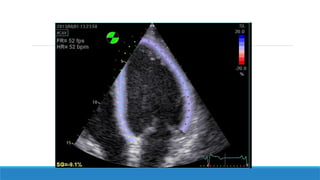

Techniques d’acquisition des images

Etape 1:

Obtenir des images de l’oreillette gauche en 4 cavités.

57

Etape 2:

Un traçage des contours endocardiques de l’oreillette gauche est réalisé

manuellement par l’opérateur et les contours épicardiques sont tracés

automatiquement par le logiciel, ainsi; une zone d’intérêt est crée.

58

Etape 3:

La paroi de l’oreillette gauche est divisée en 6 segments et le logiciel fait valider ou

non la zone de traçage réalisé pour chaque segment, une fois tous les segments sont

validés, la zone d’intérêt est approuvée et l’étude peut être réalisée.